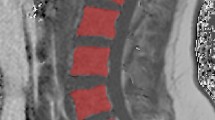

Regions of interests (ROIs) were manually drawn in the midsagittal slice of the bone marrow compartment for each vertebra in the magnitude images and then transferred to the PDFF maps and exported using the Software OsiriX (Pixmeo, Bernex, Switzerland) and Horos (The Horos Project, www.horosproject.org). Reproducibility of these measurements has been reported previously with an absolute precision error of 1.7% averaged over C3–L5 [17].

Figure 2 shows representative PDFF maps in patients with increasing age, i.e. from a 0.4-year-old male to a 6.4-year-old female: PDFF maps show a decreased VBM PDFF from the lumbar to the cervical region within the same subject and cross-sectionally with age as well.

Five representative full spine PDFF maps picked from the five youngest age groups showing a 0.4-year-old male, 0.8-year-old male, 2.3-year-old female, 3.5-year-old female, and 6.4-year-old female, respectively. Note the increase in PDFF over age and from cervical to lumbar spine. PDFF in the under-1-year-olds is nearly indistinguishable from 0%. In the 2.3-year-old the outlines of the L-spine and lower T-spine vertebrae start becoming visible in the PDFF map, whereas the upper T-spine and C-spine vertebrae still show a low PDFF. PDFF proton density fat fraction, y/o year-old